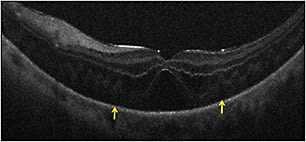

In the PIONEER study, macular indications for surgery, such as macular hole (23%) and ERM (35%), were most common. Retinal detachment and proliferative diabetic retinopathy were also frequent indications for surgery. In membrane peeling cases, iOCT successfully demonstrated completion of peel or residual membranes (Figure 2).

Figure 2. Intraoperative OCT and macular holes. (Top) Preincision intraoperative OCT B-scan revealing full-thickness macular hole (red asterisk). (Bottom) Postpeel intraoperative OCT B-scan revealing expansion of the subretinal hyporeflectivity band between the photoreceptor layers and the retinal pigment epithelium (yellow arrows).

In macular hole cases, alterations in hole geometry were noted, and increased hyporeflectivity in the subretinal space was demonstrated, similar to previous studies.1,4,6 Partially peeled internal limiting membrane was often identified as a curled, hyperreflective, thin band on the B-scan.1,6

For ERM cases, residual membranes could be identified, and alterations to retinal architecture were also noted (Figure 3, page 28).1,4 Following membrane peeling, changes in the distance between the photoreceptor layers and the retinal pigment epithelium were qualitatively visualized, similar to previous descriptions.1,4,9 These included subtle changes in the hyporeflective band between the photoreceptor layers and the RPE, as well as more significant changes in full-thickness retina.1,9